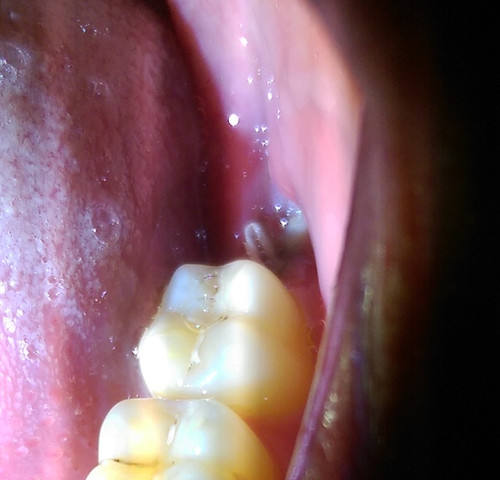

Je größer und vor allem tiefer die Wunde desto größer ist das Risiko einer gestörten Heilung. Der Kieferknochen wird dabei leicht gedehnt so dass der Zahn sich lockert. Nun die Wunde an sich sieht zwar besser aus aber auf einer bestimmten Stellen bildet sich son weißes Zeug.

Das Weiße das zu erkennen ist ist definitiv Zahnfleisch. Ein weißlicher Belag bilden müssen Sie sich keine Sorgen machen. Kiefer eine erhebliche Wunde.

Heute habe ich die Wunde überprüft und gesehen das sie sich wieder schließt aber was mich irritiert ist das an einer Stelle der Wunde das Zahnfleisch weiss ist. 5-7 Tagen können die Fäden gezogen werden.

Zahn Gezogen Ist Die Wunde Entzundet Gesundheit Zahnarzt Entzundung